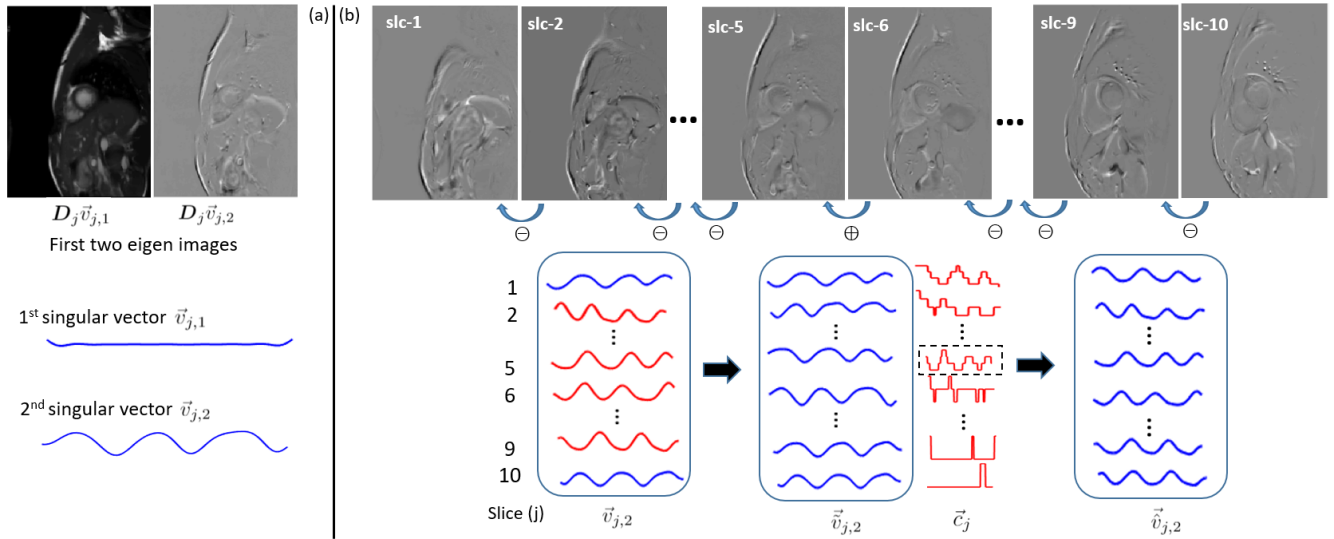

Consider an image series with frames and pixels per frame. The image series from the slice can be represented as a matrix , with each column corresponding to a single frame. First, a low pass filter is applied along the temporal dimension to suppress the higher frequency components, e.g., from the cardiac motion. Second, the eigen decomposition of is performed to obtain right singular vectors, , of . These singular vectors capture different motions present in , including the respiratory motion. Third, “eigen image” from the slice is obtained by and can be interpreted as a projection of the image series on the corresponding motion defined by . As shown in Fig. 1 (a), the first singular vector, , corresponds to the temporal average and the second singular vector, , captures the respiratory motion. For further processing, we only consider the second eigen image, , and the second singular vector, , from each slice.

We adopt a two-step procedure to resolve sign ambiguity in the respiratory motion from multi-slice CMR. In the first step, we adjust the sign of all slices () with respect to the first slice (). To this end, we estimate Pearson correlation coefficient, , between and and adjust the sign of based on , where represents the singular vector from the slice after the sign correction. This process is repeated for all values of as depicted in Fig. 1 (b). Upon the conclusion of this step, the sign of is consistent across slices but is still arbitrary with respect to the directionality of the respiratory motion and thus cannot distinguish inspiration from expiration. In the second step, we use the center-of-mass curves, , to perform the overall sign correction. Pearson correlation coefficient, , between and is estimated for all values of . Then, the sign of is adjusted by , where is the singular vector from the slice after the overall sign correction, and is the correlation coefficient with the maximal absolute value, i.e., . The curve for the slice is computed by tracking the center-of-mass in the superior-inferior (SI) direction across frames, i.e., , where represents the frame, and is the SI projection of the image series from the slice, and is the number of pixels along the SI direction. The movement of the thoracic and abdominal organs as a function of respiration is predictable in the SI direction [6]. Considering that the orientation of the imaging plane is precisely known, the SI motion in the patient coordinate system can be expressed in terms of image coordinates. Therefore, calculated from the image series can be used as a surrogate for the respiratory motion. Note, the quality of as well as correlation of with can be poor for certain slices; see Fig. 1 (b). As a result, this step by itself cannot be reliably used to adjust the sign for individual slices.